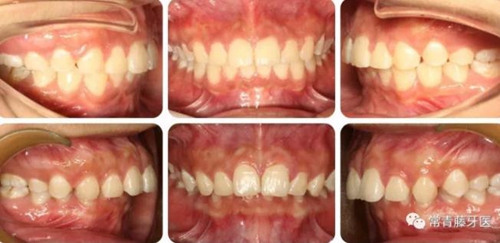

與術(shù)前對比,術(shù)后可見前牙深覆合深覆蓋得到有效改善。

上牙列得到有效內(nèi)收,上前牙凸度亦得到改善。

軟組織側(cè)貌得到明顯改善。